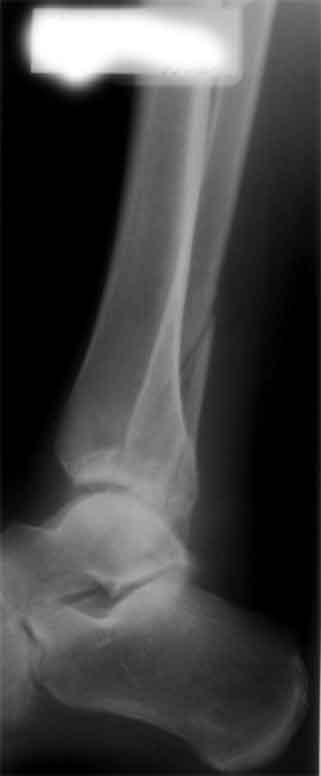

Мне кажется есть все основания попытаться сделать остеосинтез. Боль вследствие нестабильности. Нестабильность вследствие неанатомичного положения дистального отломка малоберцовой кости. Через 1,5 вполне возможно разобщить, репонировать и фиксировать длинный косой перелом наружной лодыжки. Вероятно, одновременно придется делать медиальный доступ для мобилизации внутренней лодыжки. Мы оперируем таких пациентов, функциональные (объем движений) результаты конечно хуже по сравнению с теми кого оперируем в первые 5-10 дней, но вполне удовлетворительные.

Согласен, на предоставленных рентгенограммах все основания для проведения открытого остеосинтеза.

сроки действительно небольшие, но если мы его и возьмем, то пройдет еще минимум неделя, кроме того смущает впечатление сращения н/лодыжки, похоже, что придется не разобщать,а остеотомировать, формирование оссификатов в полости сустава с медиальной стороны, да и сам пациент 1,5 месяца по поводу своей травмы сильно не напрягался